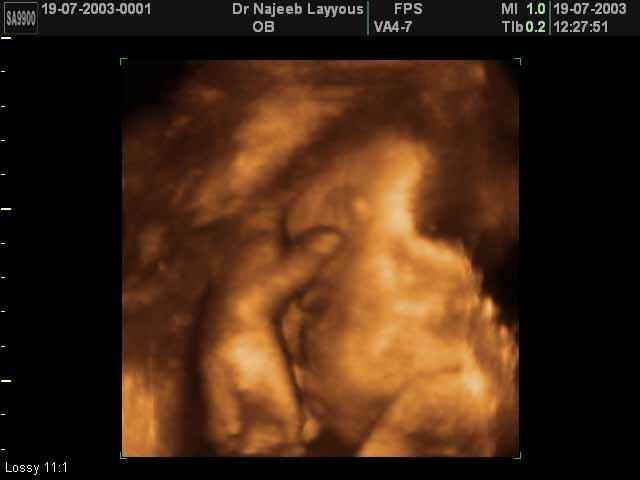

صور جانبية لرأس الجنين بجهاز الالتراساوند ثلاثي الأبعاد | الدكتور نجيب ليوس